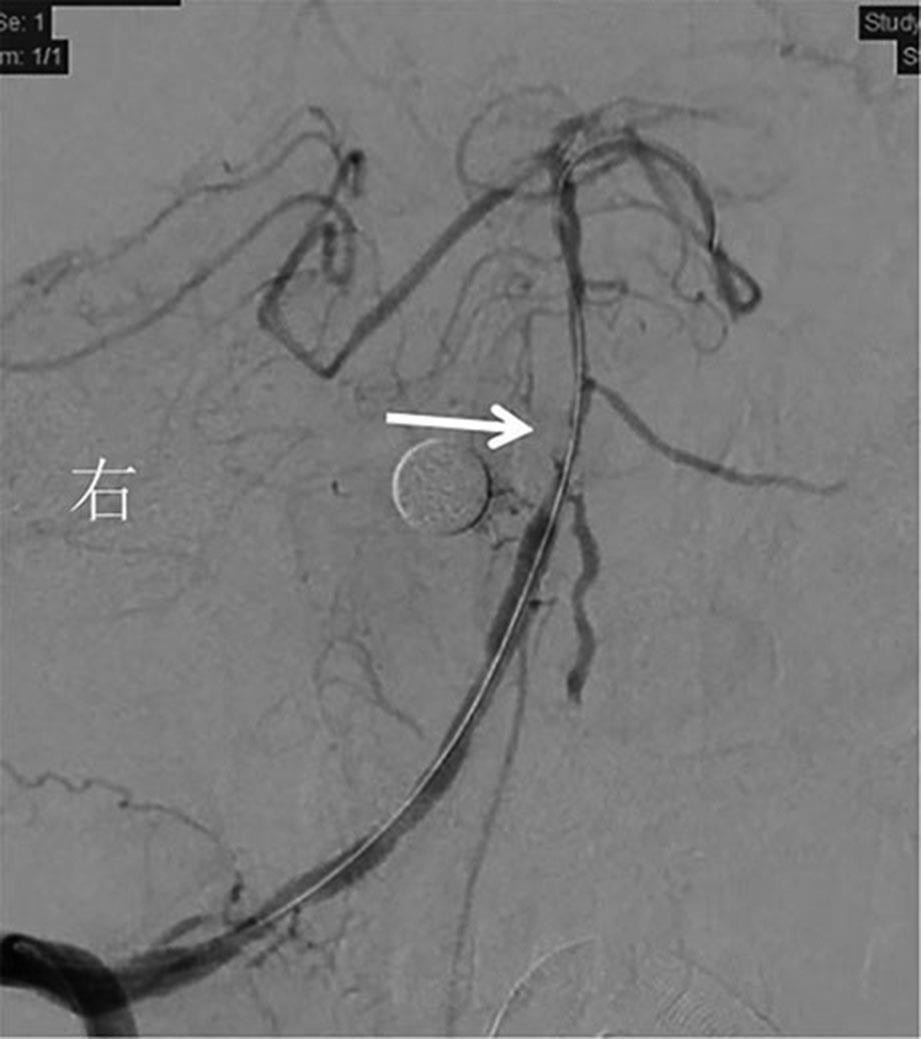

• 全身抗凝联合血管内治疗颅内静脉窦血栓形成的临床效果观察

2022, 47(7):784-789. DOI: 10.13406/j.cnki.cyxb.003064

摘要:目的 对全身抗凝联合血管内治疗在颅内静脉窦血栓形成(cerebral venous sinus thrombosis,CVST)中的临床治疗效果进行观察评估。方法 回顾性纳入2008年6月至2021年8月于海军军医大学第一附属医院接受治疗的CVST患者,根据治疗方式不同分为抗凝治疗(anticoagulation treatment,AT)组和血管内治疗(endovascular treatment,EVT)组,分析2组患者的临床资料及治疗效果。结果 共纳入54例患者,其中AT组27例,EVT组27例。EVT组血栓累及上矢状窦和直窦的患者比例、累及静脉窦数量、入院改良Rankin量表(modified Rankin scale,mRS)评分明显高于AT组(P<0.05)。治疗后2组患者凝血酶原时间、活化部分凝血酶时间较治疗前均明显延长,AT组D-二聚体水平较治疗前明显下降(P<0.05)。EVT组治疗后血管再通率明显高于AT组(P<0.05),总住院时间、重症监护室入住时间、并发症发生率、生存情况以及神经功能预后均与AT组无统计学差异(P>0.05)。2组患者治疗后mRS评分均较治疗前明显下降(P<0.05)。结论 对于血栓累及广泛、全身抗凝疗效不佳的重症CVST患者,在标准抗凝的基础上联合血管内治疗可作为一种安全有效的潜在治疗方案。